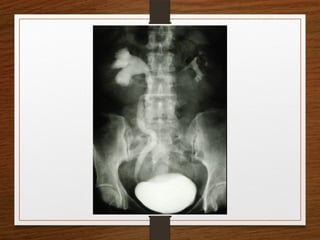

4. Renal Caluculus

5. Bladder Calculus

What are the D/D of a radiopaque shadow in this region?

• Kidney stone

• Gallstones

• Pancreatic calculi

• Foreign body

• Fecolith

• Phleboliths

• calcified lymph node

• calcified renal tuberculosis

• calcified adrenal gland

• chip fracture of a transverse process of vertebra or calcification of costal

cartilage

What are theD/D of a radiopaque shadow in this region? • Kidney stone • Gallstones • Pancreatic calculi • Foreign body • Fecolith • Phleboliths • calcified lymph node • calcified renal tuberculosis • calcified adrenal gland • chip fracture of a transverse process of vertebra or calcification of costal cartilage